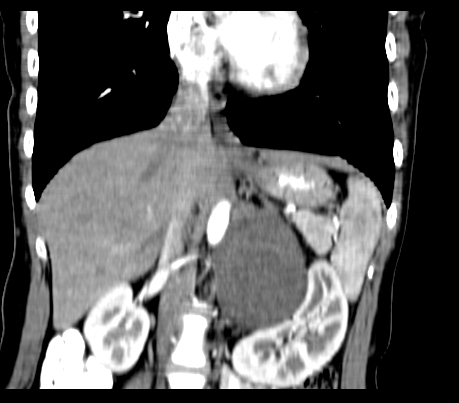

动脉期